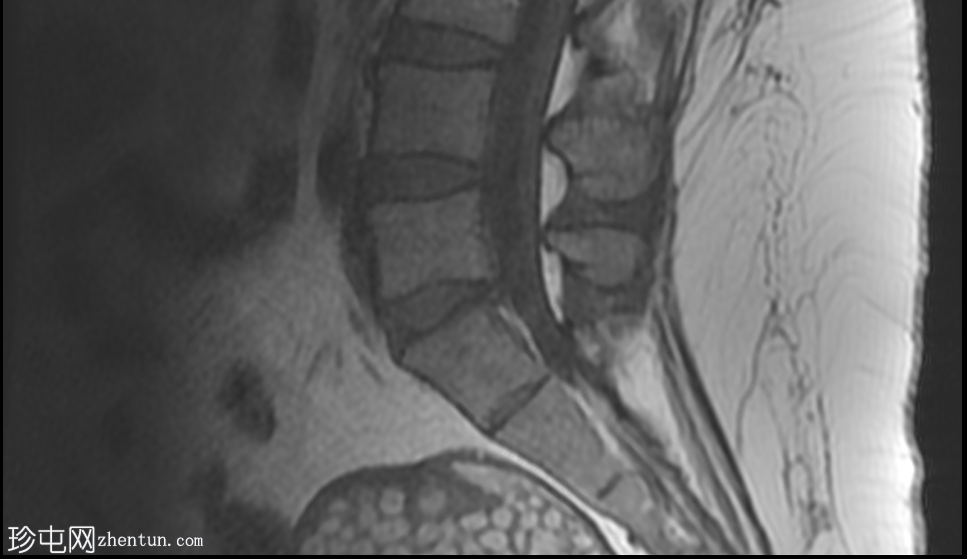

CT

轴位

平扫

可见一主要为囊性肿块,大小为10.1 x 7.3 x 8厘米,囊内含有脂肪球。囊壁可见钙化,并对直肠乙状结肠造成压迫。